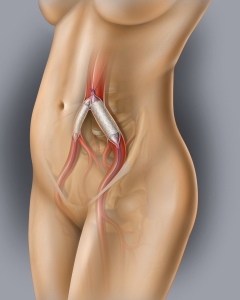

Internal Art Medical Illustration

Blending Art, Anatomy and Science for Creative Visuals

Welcome to my Patient and Professional Marketing page, where I harness the power of anatomical illustrations to educate and empower both patients and medical professionals. My unique approach combines artistry and education to convey complex surgical procedures and the utilization of medical devices in an easily understandable manner.